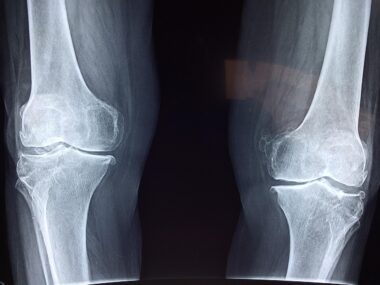

Joint problems can significantly impede daily activities, often leading to discomfort and a decline in overall quality of life. The role of Vitamin K in joint health cannot be overstated, as it aids in maintaining optimal function of cartilage and bones. When these structures are healthy, the chances of experiencing joint pain decline significantly, allowing individuals to engage in physical activities. Many may wonder about the signs of Vitamin K deficiency, which can sometimes be subtle but ultimately lead to more severe health issues. Common symptoms include easy bruising, weak bones, and increased joint discomfort, hinting at the importance of this vitamin. Therefore, reinforcing one’s diet with adequate amounts of Vitamin K can contribute to better joint function. Many vegans may find it necessary to reconsider their food choices and supplementation to ensure they receive sufficient Vitamin K. It becomes imperative to engage with nutritionists or dietitians who specialize in plant-based diets for tailored advice. Incorporating diverse vegan foods not only enhances nutrient intake but also fosters improved joint health and helps prevent various musculoskeletal disorders.

Vitamin K possesses anti-inflammatory properties that can significantly benefit joint health. Chronic inflammation often exacerbates joint pain, leading to conditions like osteoarthritis or rheumatoid arthritis. By incorporating adequate Vitamin K into the diet, individuals may find a natural way to mitigate these inflammatory responses. Research indicates that sufficient levels of Vitamin K are associated with lower markers of inflammation in the body, acting as an adjunct in joint health management. This relationship highlights the importance of not just adequate intake, but also the body’s ability to utilize Vitamin K efficiently. Regular physical activity alongside a nutrient-rich diet can enhance this synergistic effect, fostering not only joint health but overall well-being. Many vegans, therefore, can optimize their health outcomes by proactively addressing inflammation through dietary choices and lifestyle modifications. Focusing on whole, minimally processed vegan foods allows for greater nutrient absorption and bioavailability. Thus, creating a balanced approach towards nutrition goes a long way, promoting joint health and overall vitality for individuals leading a vegan lifestyle. Therefore, understanding these mechanisms encourages engagement in better dietary practices today.